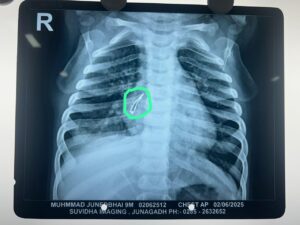

કારપેન્ટરનુ કામ કરતા મંગરોળ, જુનાગઢ ના રહેવાસી એવા શ્રી જુનેદ યુસુફ અને શ્રીમતી તબસ્સુમબેનના લાડકવાયા એવા 9 માસના નાનકડા પુત્ર મોહમ્મદને છેલ્લા ૧૫ દિવસથી ઉધરસ આવતી હતી. જુનાગઢ માં બાળરોગ તજજ્ઞ ને બતાવતા તેનો છાતીનો એક્સ-રે કરાવતા તેમાં શ્વસનનળીમાં કાંઈક હોવાની માલુમ પડ્યુ હતુ. જુનેદ ભાઇને રાજકોટની ખાનગી હોસ્પિટલ દ્વારા વધુ તપાસની ભલામણ કરવામાં આવી પણ તેનો ખર્ચ તેમને પોષાય તેમ ન હોવાથી તેમના માટે સિવિલ હોસ્પિટલ અમદાવાદ આશાની કિરણ બની જ્યાં સારવાર અર્થે બાળક ને લઇ આવતા તારીખ ૩ જૂન, ૨૦૨૫ ના રોજ બાળકને પીડીયાટ્રીક સર્જરી વિભાગ માં તાત્કાલિક દાખલ કરવામાં આવ્યુ.

સિવિલ હોસ્પિટલ, અમદાવાદના પીડિયાટ્રિક સર્જરી વિભાગના વડા ડૉ. રાકેશ જોશી તેમજ એનેસ્થેસિયા વિભાગના પ્રોફેસર ડૉ. નિલેશ અને તેમની ટીમ દ્વારા બાળકની બ્રોન્કોસ્કોપી કરી જમણી તરફ ની મુખ્ય શ્વાસનળીમાંથી એક એલઇડી બલ્બ સફળતાપુર્વક બહાર કાઢવામા આવ્યો. ઓપરેશન પછી બાળકની તબીયત ઝડપથી સુધરી રહી છે અને કોઇપણ બીજી તકલીફ વગર બાળક હવે સ્વસ્થ છે જેથી ટુંક સમય માં તેને હોસ્પિટલ માં થી રજા આપવામાં આવશે તેમ ડોક્ટરો એ જણાવ્યુ હતુ.